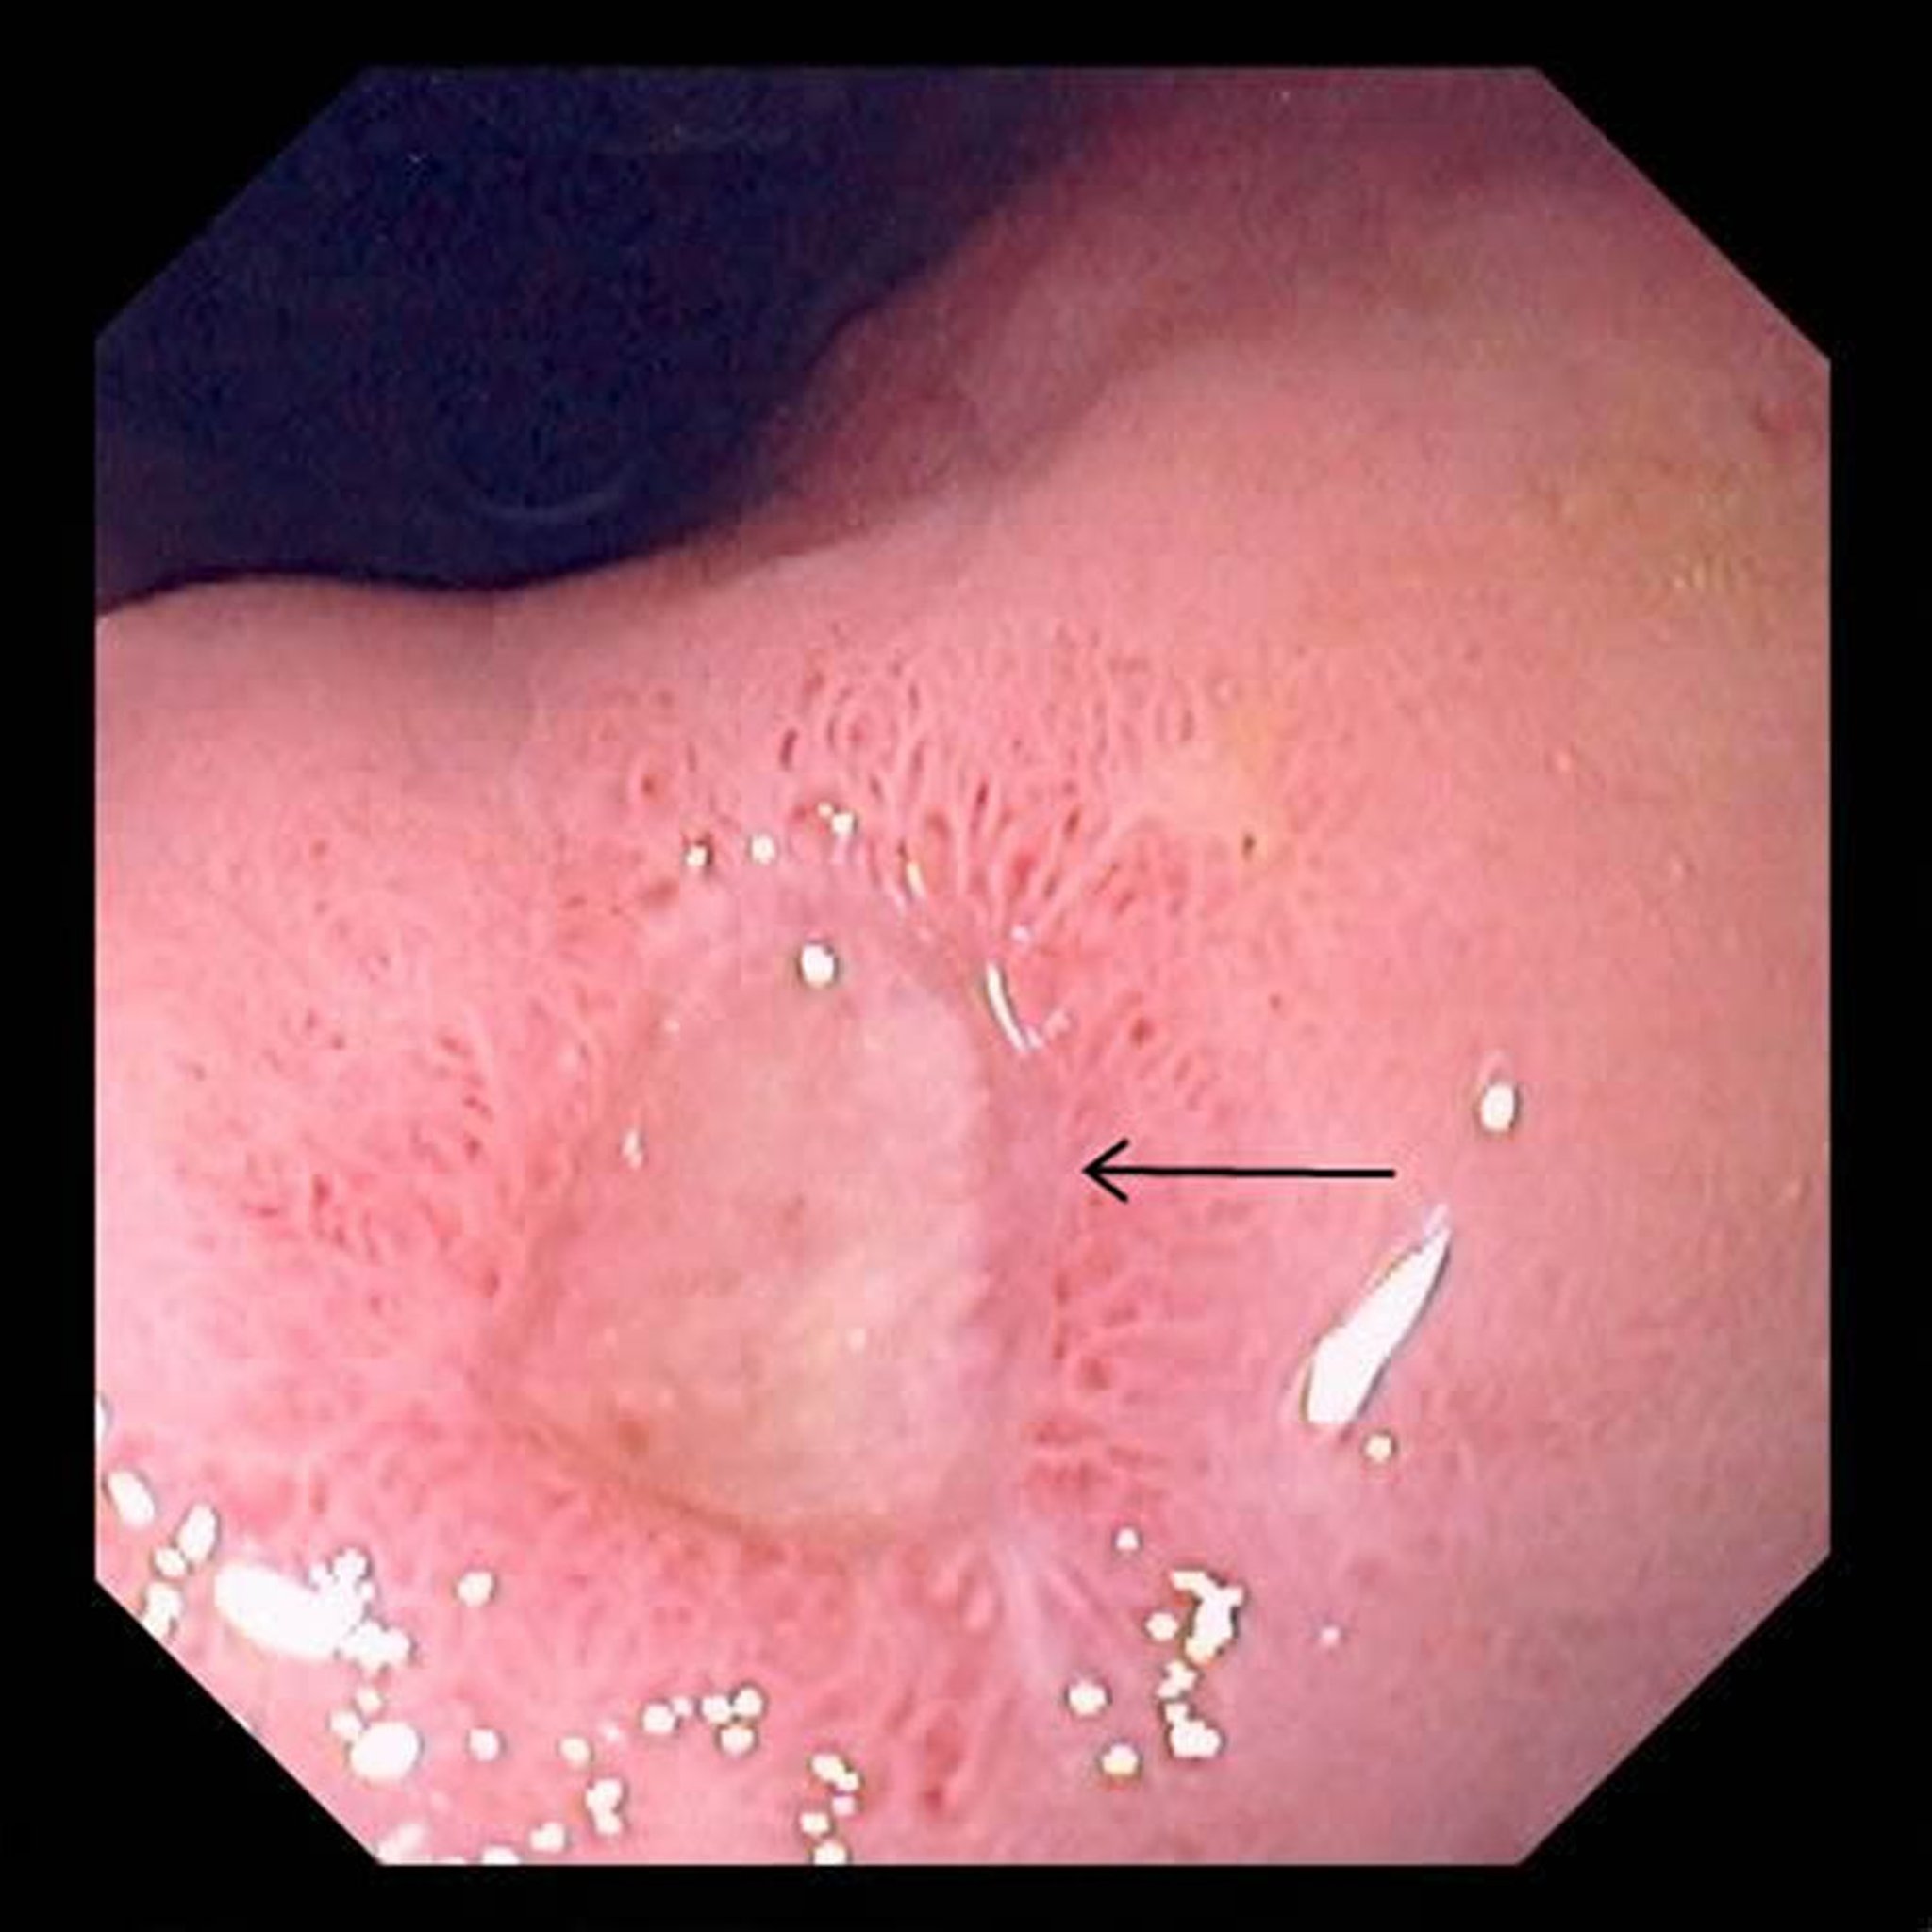

Язва желудка

На данной фотографии представлена большая язва (стрелка) в желудке.

Фотография предоставлена д-ром Дэвидом М. Мартином (David M. Martin, MD).